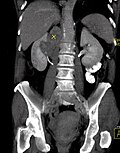

Koronal reformatierte Darstellung von Abdomen und Becken; gut zu erkennen sind u. a. die Leber und die beiden Nieren. -